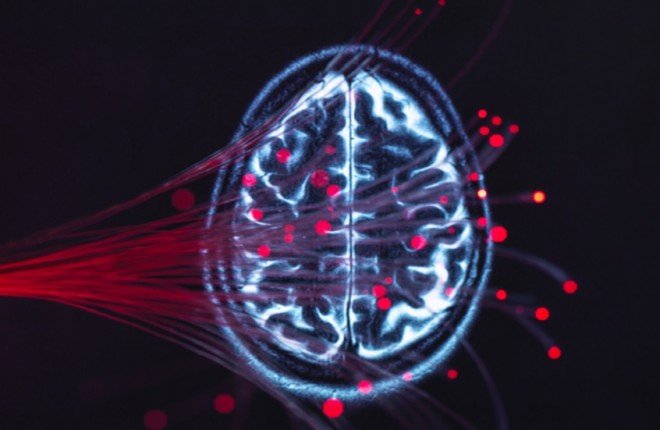

ابتكار ثوري يتيح قراءة الأفكار البشرية عبر تحليل نشاط الدماغ

كشف فريق من العلماء عن تطوير تقنية جديدة قادرة على ترجمة نشاط الدماغ إلى أوصاف نصية دقيقة لما يراه الإنسان أو يتذكره، في خطوة علمية تمهد لعصر جديد في فهم العقل البشري والتواصل مع من فقدوا القدرة على الكلام.

وأطلق الباحثون على هذا الابتكار اسم "التعليق الذهني"، وهو نهج يعتمد على نماذج لغوية متقدمة لربط الإشارات العصبية بالمحتوى النصي بشكل متكامل ودقيق.

تعتمد الطريقة على التصوير بالرنين المغناطيسي الوظيفي (fMRI) لتسجيل أنماط النشاط في الدماغ، ثم تستخدم خوارزميات لغوية مثل RoBERTa-large وDeBERTa-large لتحليل السمات الدلالية وتحويلها إلى جمل تصف ما يدور في ذهن الشخص.